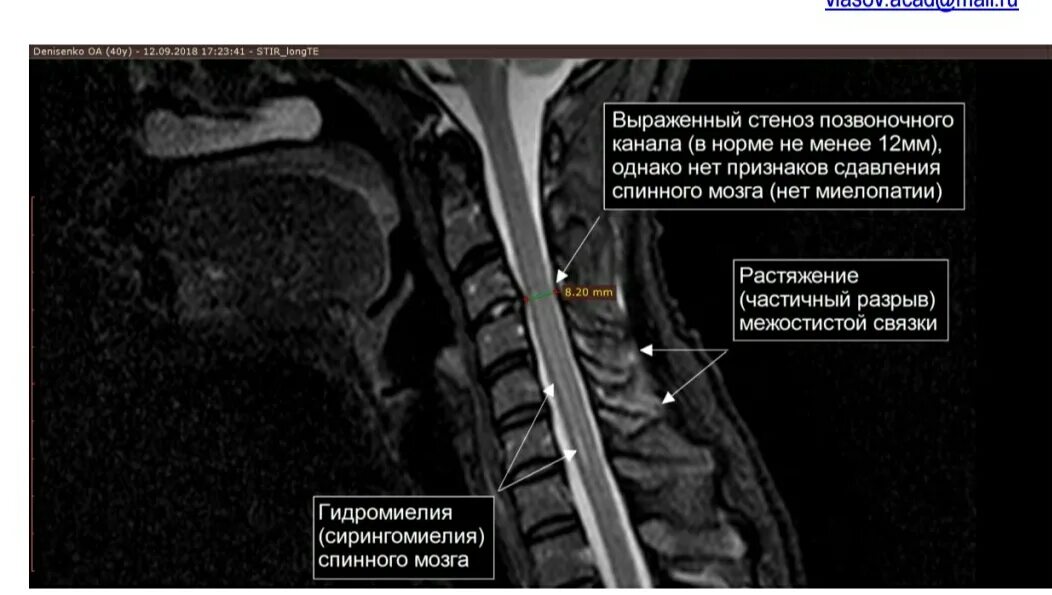

Киста в грудном отделе позвоночника